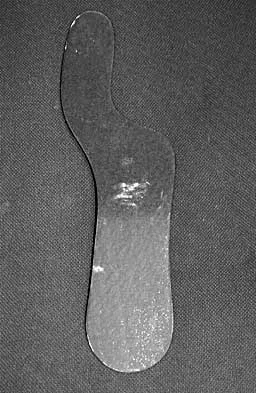

The orthosis shown in Figure 47 is commonly used for

Explanation